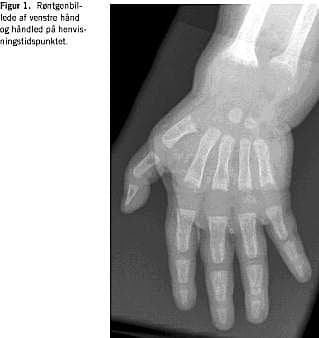

Behandlingen ændredes til 1 mg alfacalcidol. Herefter steg S-calcium-ion og total S-calcium, S-basisk fosfatase og S-PTH faldt (Tabel 1). Efter syv måneder var S-calcium og D-vitamin-stofskiftet normaliseret. Efter tre måneder var der radiologiske tegn på opheling (Figur 2), og efter knap et års behandling var der yderligere opheling af de påviste rakitisforandringer (Figur 3). Patienten og forældrene blev undersøgt for CYP27B1-genet (GeneDx lab. USA). Patienten var homozygot for en 7 bp-duplikation i exon 8 af CYP27B1-genet. Begge forældre var heterozygote for mutationen, havde normalt niveau af S-calcium, S-fosfat og P-1,25 dihydroxy-D-vitamin.

Knogleforandringerne blev ophelet ved behandling med fysiologiske doser af alfacalcidol, en aktiveret D-vitamin-metabolit. Behandlingen er livslang. Det tilstræbes at holde S-calcium på et niveau, der kan holde S-PTH inden for referenceområdet. Er S-calcium for højt, øges risikoen for nefrokalcinosis [5].